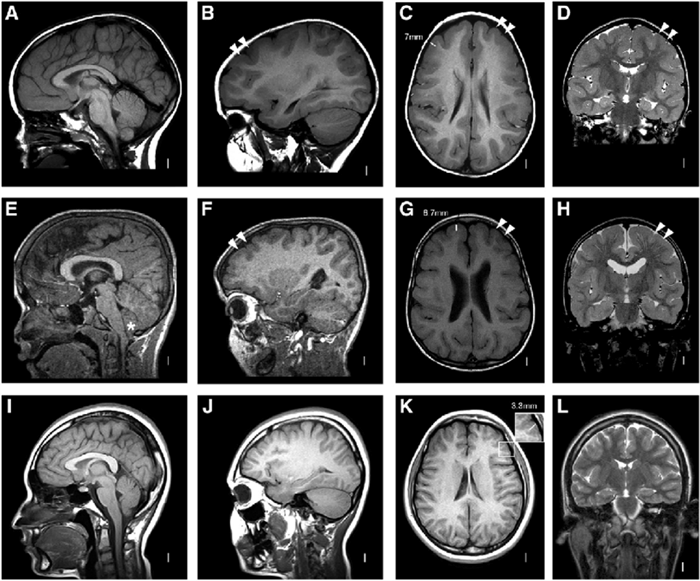

Систематизация изменений на МРТ при рассеянном склерозе привела к созданию так называемых рекомендации MAGNIMS к критериям постановки диагноза рассеянного склероза Мак Дональда. По этим рекомендациям мы можем ускорить постановку диагноза, не дожидаясь очередного обострения:

- Рассеянность (диссеминация) в пространстве определяется при наличии очагов в двух из указанных ниже пяти областей центральной нервной системы:

- перивентрикулярно (в области, примыкающей к желудочкам головного мозга) более 3-х очагов

- кортикально-юкстакортикально (очаги, расположенные практически в коре головного мозга) ≥ 1 очага

- инфратенториально ≥ 1 очага

- в спинном мозге ≥ 1 очага

- в зрительном нерве ≥ 1 очага

- появление нового очага по сравнению с предыдущим исследованием

- очаг на Т2-изображении, накапливающий контраст на Т1-изображении

- выявление при одном исследовании очагов накапливающих и не накапливающих контраст

Это МР-рекомендации к критериям Мак Дональда, позволяющие систематизировать данные МРТ и использовать их для диагностики заболевания. Например, у Вас одно обострение, и Вы с этим обострением пришли к врачу (например, с онемением руки). Клинических данных, подтверждающих рассеянность в пространстве и времени нет: одно обострение, один симптом, указывающий на поражение одного отдела головного мозга. Если бы у нас не было МРТ, то Вас отправили бы домой ждать возникновения следующего обострения. При этом весь период ожидания Вы бы не получали лечения. Если через несколько месяцев или лет у Вас снова возникнет ухудшение, например, ослабеет правая нога, то критерии рассеянности во времени (наличие двух обострений) и в пространстве (клинические указания на поражение разных отделов ЦНС – сначала онемение руки, затем слабость ноги) будут соблюдены и Вам выставят диагноз рассеянного склероза и только после этого начнут лечение. Но весь период между первым и вторым обострениями Вы не получали лечение и рассеянный склероз продолжал у Вас развиваться. В нынешнее время при первом обострении Вас отправят на магнитно-резонансную томографию с контрастом, во время которой, например, обнаружат три перивентрикулярных очага, один очаг в спинном мозге, а из трех перивентрикулярных один будет копить контраст. Тогда будет доказана рассеянность в пространстве – очаги расположены в разных областях и во времени – на одном исследовании есть активный очаг и неактивные очаги. Тогда, не дожидаясь следующего обострения, Вам выставят диагноз рассеянного склероза и начнут лечение раньше. А залог успеха в лечении – раннее его назначение. Другой пример: у Вас было два оптических неврита слева. Клиническими данными за наличие двух обострений доказана рассеянность во времени, но, так как поражена только одна функциональная зона – левый зрительный нерв, то нам нужны дополнительные доказательства рассеянности в пространстве. Вас отправят на МРТ и найдут, например, один очаг в зрительном нерве и три перивентрикулярных. Таким образом, мы сможем доказать рассеянность в пространстве и выставить диагноз РС. Но все-таки на одних критериях диагноз не выставляется. Критерии Мак Дональда и рекомендации MAGNIMS нужны нам в качестве помощников, но в каждом случае с каждым пациентом нужно провести работу, обследовать, применить весь свой опыт и только после этого установить диагноз демиелинизирующего заболевания. Каждый случай диагностики по-своему уникален.